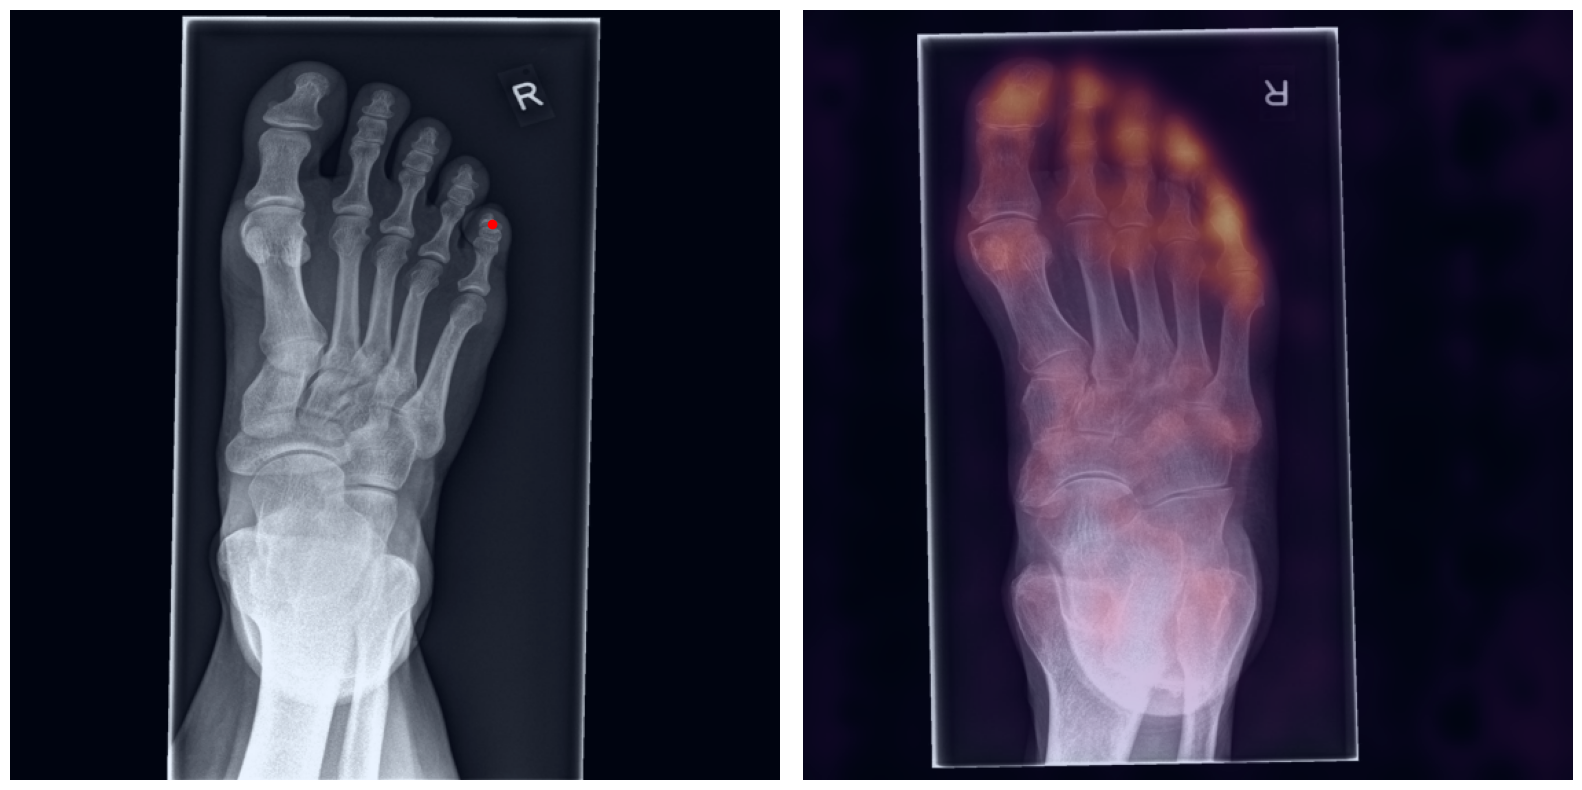

This study presents a zero-shot artificial intelligence (AI)-based approach for automated landmark matching in radiographs, designed to improve scalability and reliability in deriving musculoskeletal (MSK) measurements across various anatomic regions and conditions. Key anatomic landmarks were manually identified under expert supervision, building the basis to automatically derive pertinent angle and distance measurements. Using one patient's radiograph as a reference, a robust AI-based feature matching approach establishes dense matches between the reference and unseen target images. Reference landmarks are transferred along the dense matching, resulting in precise landmark placement and automated calculation of MSK measurements within an entire patient cohort. The results demonstrate versatile and robust application without requiring anatomy-specific training, while remaining stable with in the presence of orthopedic implants.

Artificial intelligence (AI) has shown great potential in assisting radiologists with musculoskeletal (MSK) assessments across various anatomical regions1,2,3,4. However, most existing tools are narrowly tailored for specific anatomies or rely on segmentation-based methods as a basis. To address these limitations, we propose a versatile and generalist AI-based approach for landmarks matching. In contrast to typical generalist landmark matching approaches that depend on automatically identified, optimally descriptive landmarks5,6,7, our use-case has to be based on manually selected landmarks tailored for MSK measurements. As these landmarks are potentially subotimal for precise matching, we employ an AI-based method8 that first performs multi-scale dense image matching between the reference and target images independently of the landmarks. The AI uses a combination of transformer and convolutional neural networks to establish a multi-resolution descriptive feature representation of each position within the images, allowing to define correspondences between the reference and target images. In a subsequent step, landmark positions are transferred to the target image based on these correspondences, with the determination of final locations benefiting from the redundancy of the dense matching. This enables robust automation of landmark matching from a reference patient across an entire cohort of target patients. The approach is anatomy-agnostic, enabling the use of the same backbone model for a wide range of anatomical regions and MSK measurements. For more detailed information we refer to our paper.

Once a correspondence between the reference and target radiographs is established, landmark matching can be performed in real-time. This process enables the alignment of individual points and allows for the definition of a predefined set of landmarks that can be mapped onto the target patient. These predefined landmarks can be customized for the automated calculation of specific measurements, which, once defined on a reference patient, can be consistently and automatically transferred to any radiograph within the target cohort.

The process of establishing a dense match between two images relies on abstract feature representations for each position in both the reference and target images. To better understand which information is encoded by the AI, we examined the feature similarities between a specific position within the reference image and the entire target image. Our findings show that the AI captures both semantic and texture features. The matching process utilizes this encoded information, along with precise positional data, to create a reliable mapping between the images.